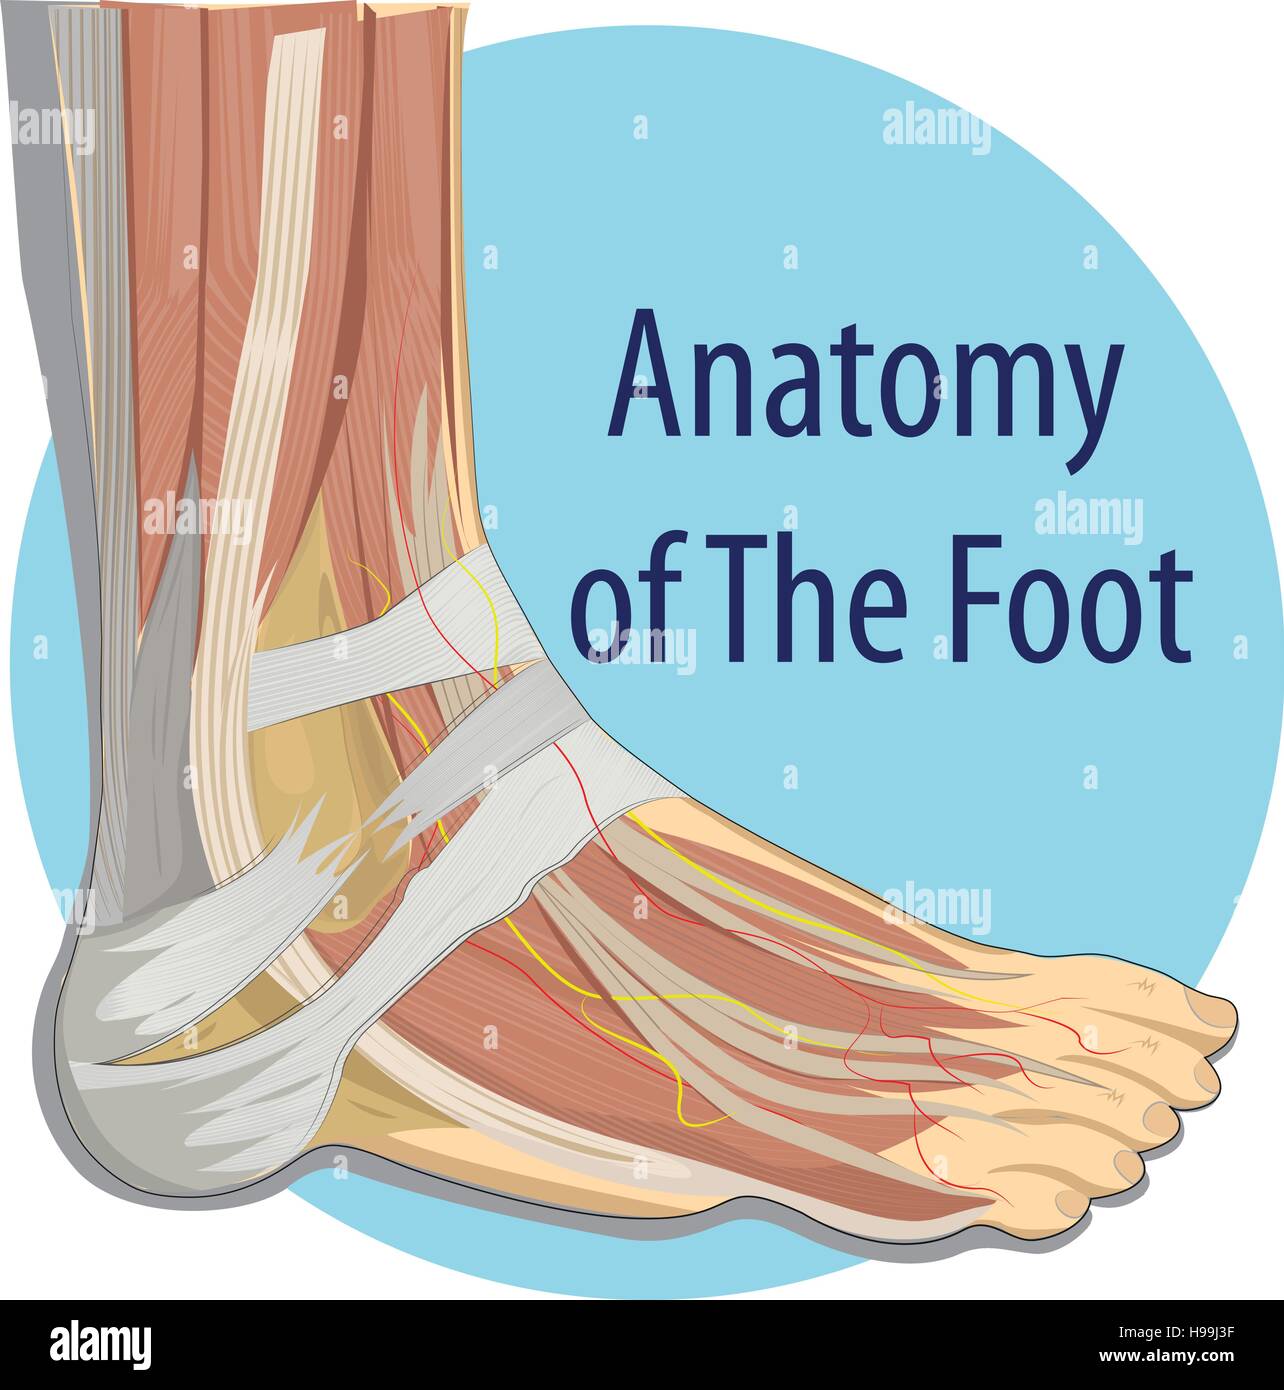

RF2ABM669–La médecine et les soins de l'illustre le tableau, les droits de l'anatomie du pied : Peau et tissus ectodermaux, os, muscles nerfs, vaisseaux sanguins

RFTCW7GT–L'articulation de la cheville, les tendons de la cheville anatomie pied eps vector illustration infographie 10